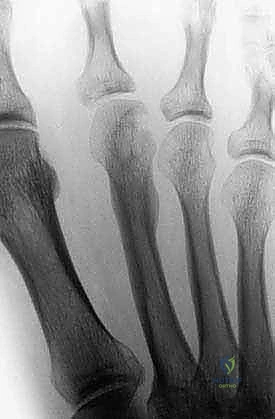

FIG 2 • A. Benign tumors can show cortical thickening, mimicking a stress fracture. In this case, it was a benign lesion of the second metatarsal.